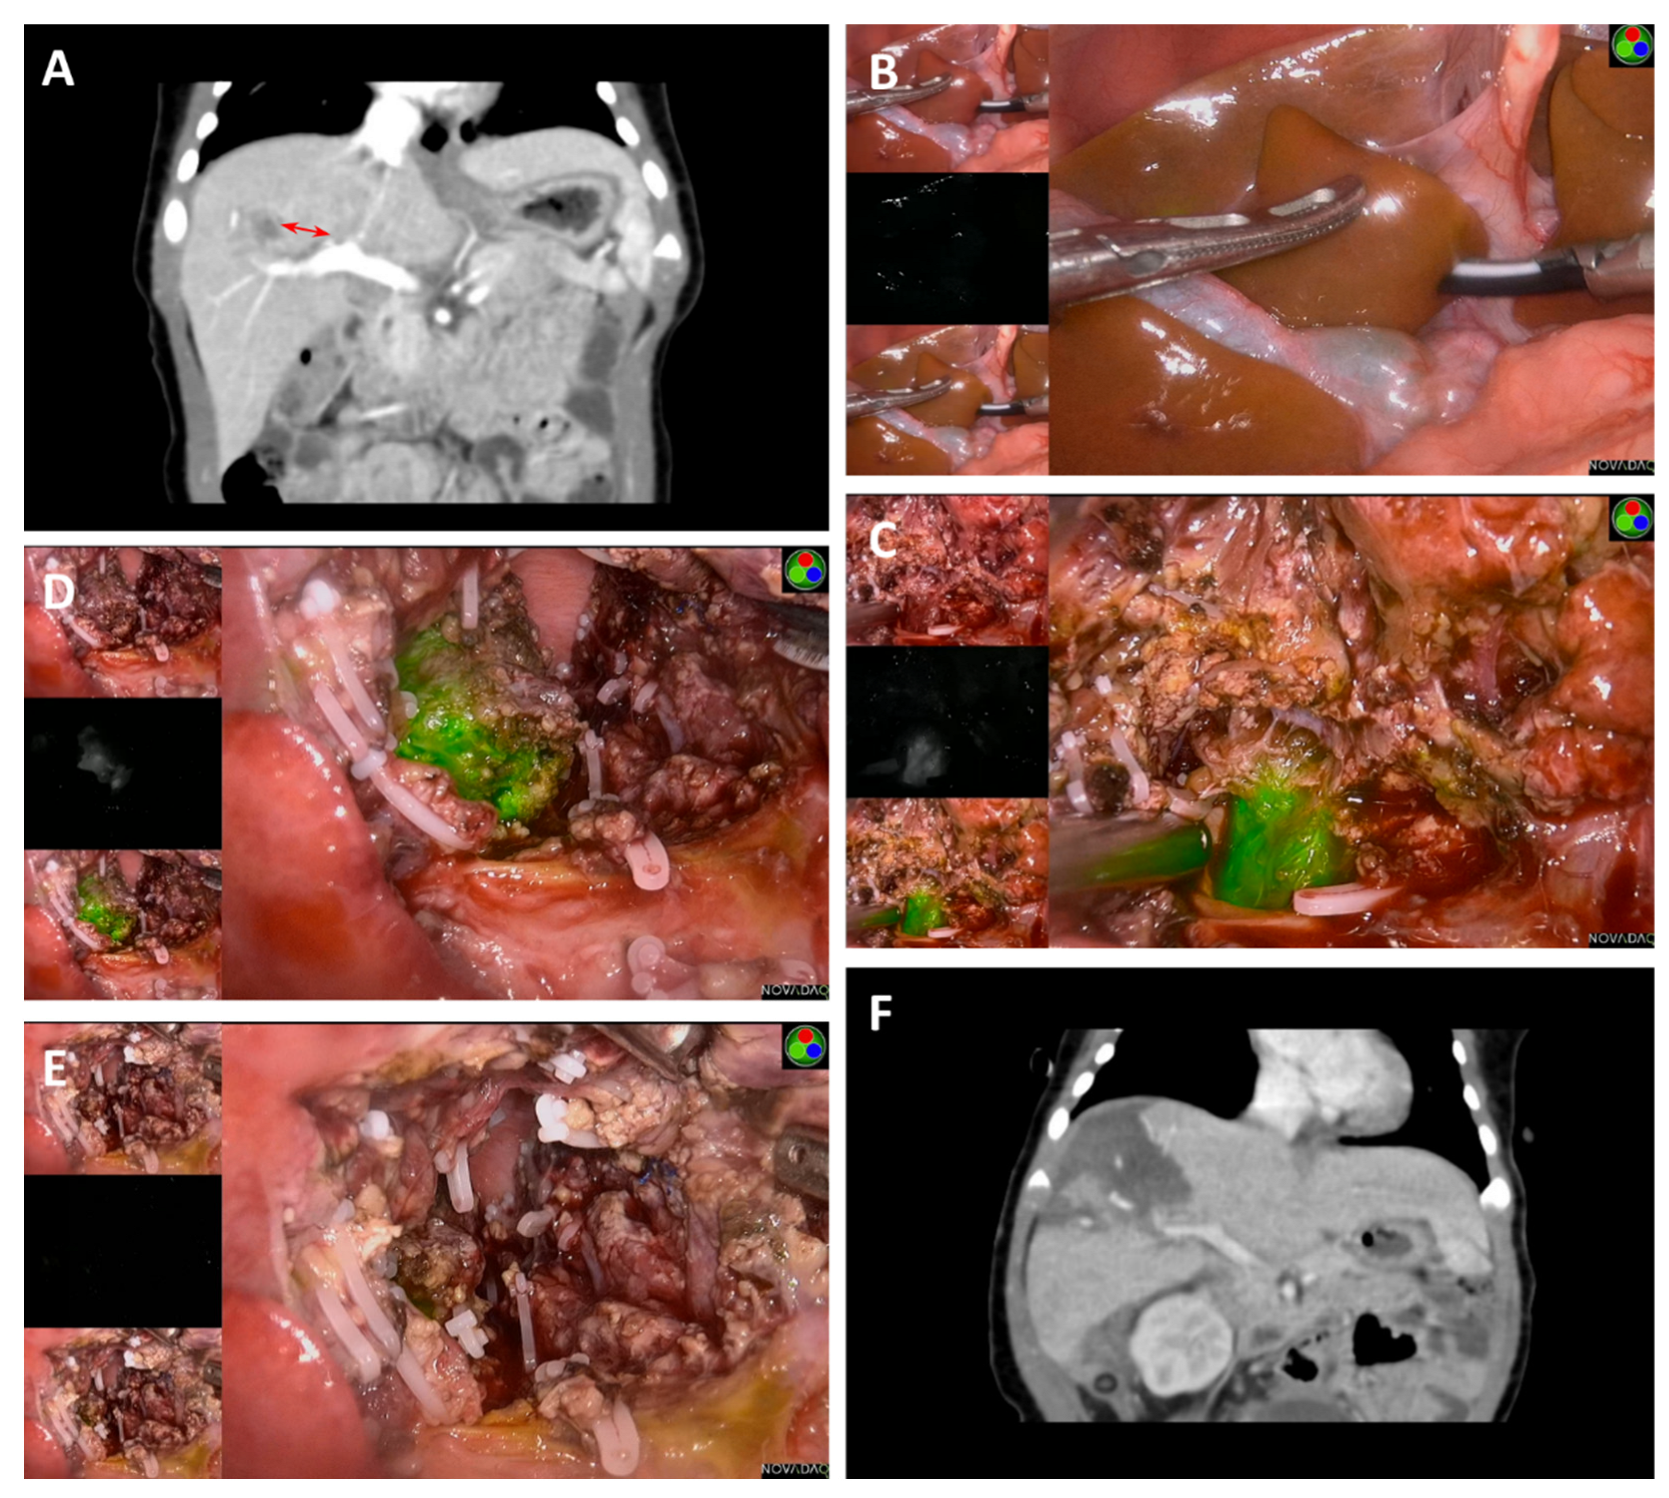

| 1 | Male | 14 M | III | II | 4 C5VD | 21,492 | 75 | 48 h | 0.5 | 0mm | PH (S5,S6) | 250 | Fetal and embryonal | 1127 | Alive without disease |

| 2 | Male | 22 M | III | II | 3 C5VD | 60.37 | 70 | 48 h | 0.5 | 0mm | PH (S5,6,7) | 295 | Embryonal | 1085 | Alive without disease |

| 3 | Male | 9 M | III | II | 4 C5VD | 2468 | 65 | 48 h | 0.5 | 0mm | RH | 410 | Epithelial and mesenchymal | 1012 | Alive without disease |

| 4 | Male | 36 M | III | II | 3 CCD + 2 ICE | 82.5 | 87 | 48 h | 0.5 | 0mm | CBS | 570 | Fetal | 779 | Alive without disease |

| 5 | Male | 13 M | III | II | 4 C5VD | 398.6 | 47 | 48 h | 0.5 | 0mm | PH (S4a) | 310 | Fetal | 448 | Alive without disease |

| 6 | Male | 3 M | II | I | 2 C5VD | 1025 | 25 | 48 h | 0.5 | 11.5mm | PH (S8) | 430 | Epithelial and mesenchymal | 259 | Alive without disease |

| 7 | Female | 13 D | I | I | None | 31,178 | 30 | 48 h | 0.5 | 0mm | LLS | 250 | Fetal | 247 | Alive without disease |